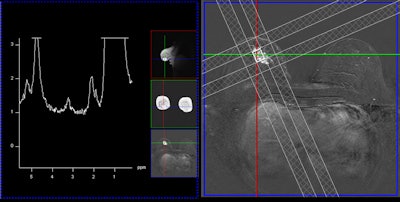

A single-voxel 1.5-tesla spectroscopy image of an invasive lobular carcinoma. The left image depicts the spectrum, i.e., the chemical components of the cancer, and the peak in the middle at about 3.23 ppm is due to tumor-specific choline metabolites. The right image shows the measurement voxel inside a contrast-enhancing mass (the cancer).

A single-voxel 1.5-tesla spectroscopy image of an invasive lobular carcinoma. The left image depicts the spectrum, i.e., the chemical components of the cancer, and the peak in the middle at about 3.23 ppm is due to tumor-specific choline metabolites. The right image shows the measurement voxel inside a contrast-enhancing mass (the cancer).Another presenter at the session, Dr. Alexandra Athanasiou from the department of radiology at the Institut Curie in Paris, will discuss ultrasound elastography, which maps breast lesion stiffness.